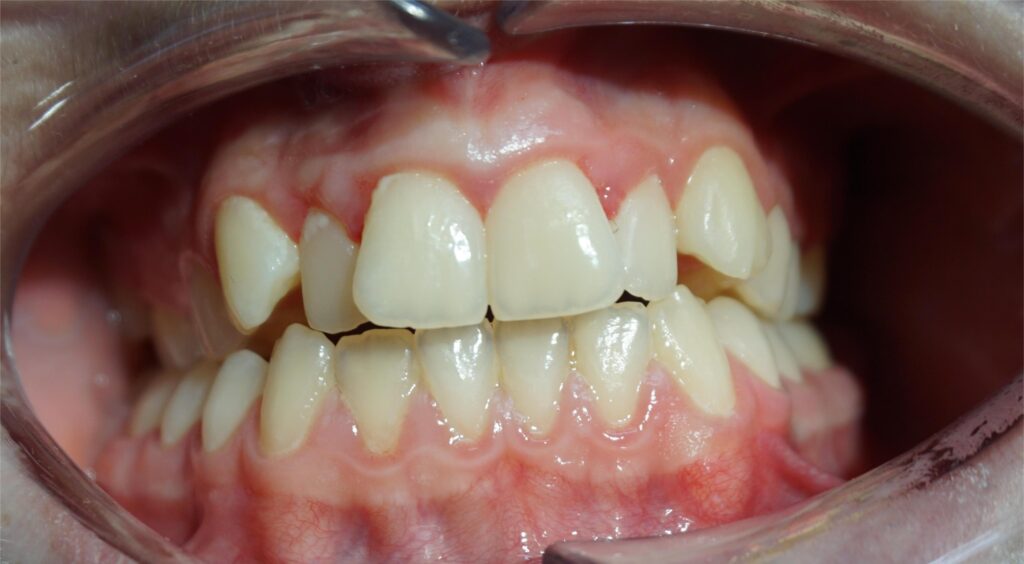

W Altom Clinic prowadzimy leczenie ortodontyczne dorosłego Pacjenta ze znacznym stłoczeniem zębów w obu łukach zębowych, powikłanym jednostronnym zgryzem krzyżowym bocznym. Taka wada zgryzu wpływa nie tylko na estetykę uśmiechu, ale również na funkcję żucia, symetrię twarzy oraz na całą postawę ciała.

Dzięki konsekwentnemu przestrzeganiu zaleceń i regularnym wizytom kontrolnym leczenie przebiega zgodnie z planem. Obecnie jesteśmy na końcowym etapie terapii – przed zdjęciem aparatu. Osiągnięto już znaczącą poprawę pozycji zębów oraz korektę zgryzu krzyżowego.

Finishing czyli końcowa faza leczenia ortodontycznego ma na celu uzyskanie prawidłowych kontaktów zębowych i zapewnienie stabilności efektów leczenia w przyszłości. Już teraz widać wyraźną różnicę – zęby są wyrównane, a łuki zębowe harmonijne i symetryczne.